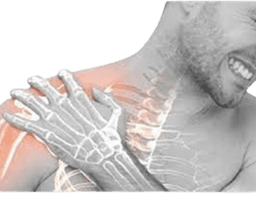

Brachial Plexus Surgery

The brachial plexus works to convey movement and sensory signals from the upper spinal cord in the neck down into the arms and hands. Essentially, this is a network of nerves that is useful to convey signals. However, an accident or trauma to the neck or shoulder can injure the brachial plexus, which also causes pain, weakness, numbness, or paralysis in the arms or hands. -br In some cases, some brachial plexus injuries are able to cure on their own and restore normal or near-normal function. On the other hand, in the case of a severe injury, brachial plexus surgery is considered to be the best treatment to relieve the symptoms of pain and restore sensation and mobility.